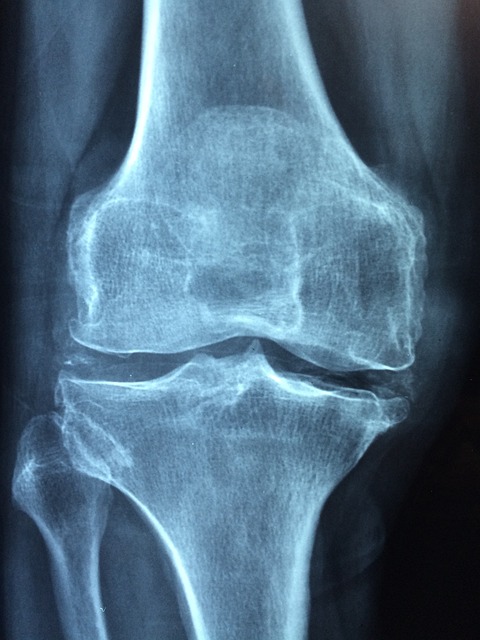

🦴 4. 관절 통증 & 근육 약화

→ 에스트로겐이 뼈 건강에도 관여하는 호르몬이라서,

갱년기엔 골다공증, 손목통증, 무릎 시큰거림도 종종 나타나요.